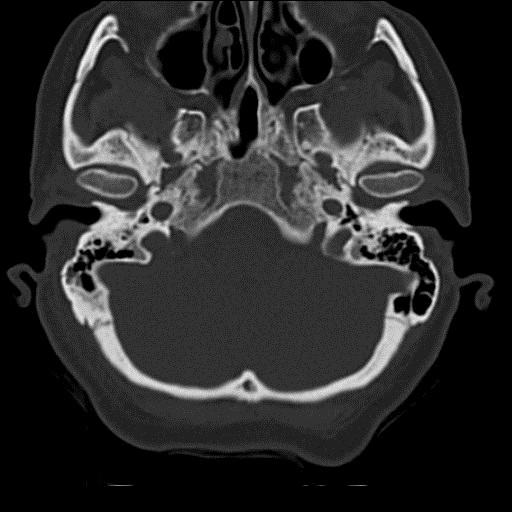

А можете показать перелом стрелкой на аксиальных сканах?

Да. Только это не аксиалы, а выровненные и несколько скошенные реконструкции для лучшего отображения линии перелома.

Известно место удара, есть линия перелома на своде. А воздух в черепе и шее заставил поковыряться